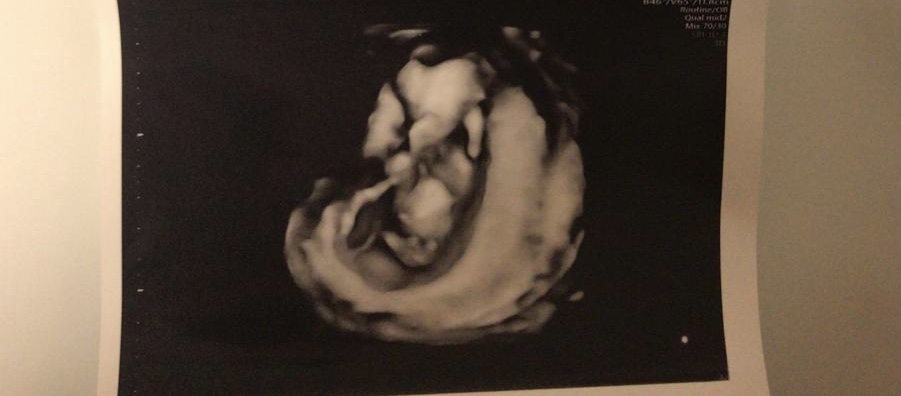

Ihr Lieben, ich bitte um eure Einschätzung, bin SSW22, lt Arzt eher ein Mädchen, ich bin trotzdem noch unschlüssig und neugierig auf eure Meinungen, danke😊